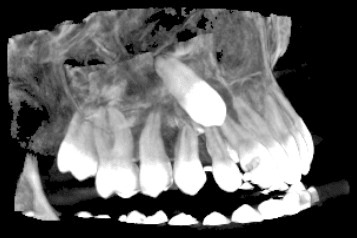

3D скенер на зъби – една челюст

Триизмерният образ на цяла челюст (горна или долна) позволява анализ на различни патологични състояния в челюстта като възпаления, тумори, кисти, фрактури и др. Използва се широко при поставянето на няколко импланта на едната челюст, определяне на точното положение на ретинирани зъби, както и за изработка на хирургични водачи.